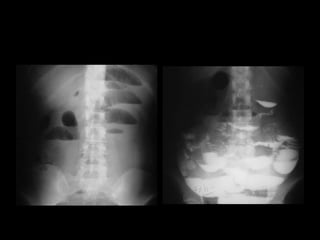

Radiografía de Tórax. Radiografías de abdomen simple de pie Radiografías contrastadas Ecografía abdominal Tomografía Resonancia Magnética

Radiografía de Tórax.Radiografías de abdomen simple de pie Radiografías contrastadas Ecografía abdominal Tomografía Resonancia Magnética